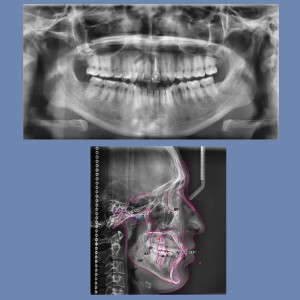

SERVICIOS 2D